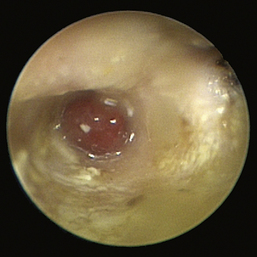

image

Figure 20-11 Bulging pars tensa in a dog with otitis media.

(Courtesy of Dr. Lynette Cole, The Ohio State University, Columbus, Ohio.)

Figure 20-12 Scaly pars tensa in a dog with otitis media.